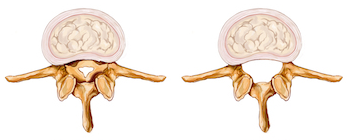

脊椎管道狹窄症

脊椎管道狹窄症(Spinal Stenosis)是其中一個引致坐骨神經痛的原因,通常發生在年長一族,屬於退化性病理。其實,脊椎狹窄是指脊椎管道丶神經根管道收窄丶脊骨的小關節位肥大變厚丶脊椎韌帶退化及骨刺増生,壓著管內裹的脊椎神經線而産生痛症。

脊椎管道狹窄 正常脊椎管道

脊椎管道狹窄可發生在任何的脊椎部位,但最常見都是發生在腰部,一般年長人士都有脊椎狹窄的情況出現,但不是每一位患脊骨狹窄的長者都會出現痛楚,除非壓著神經線,痛楚才會產生。